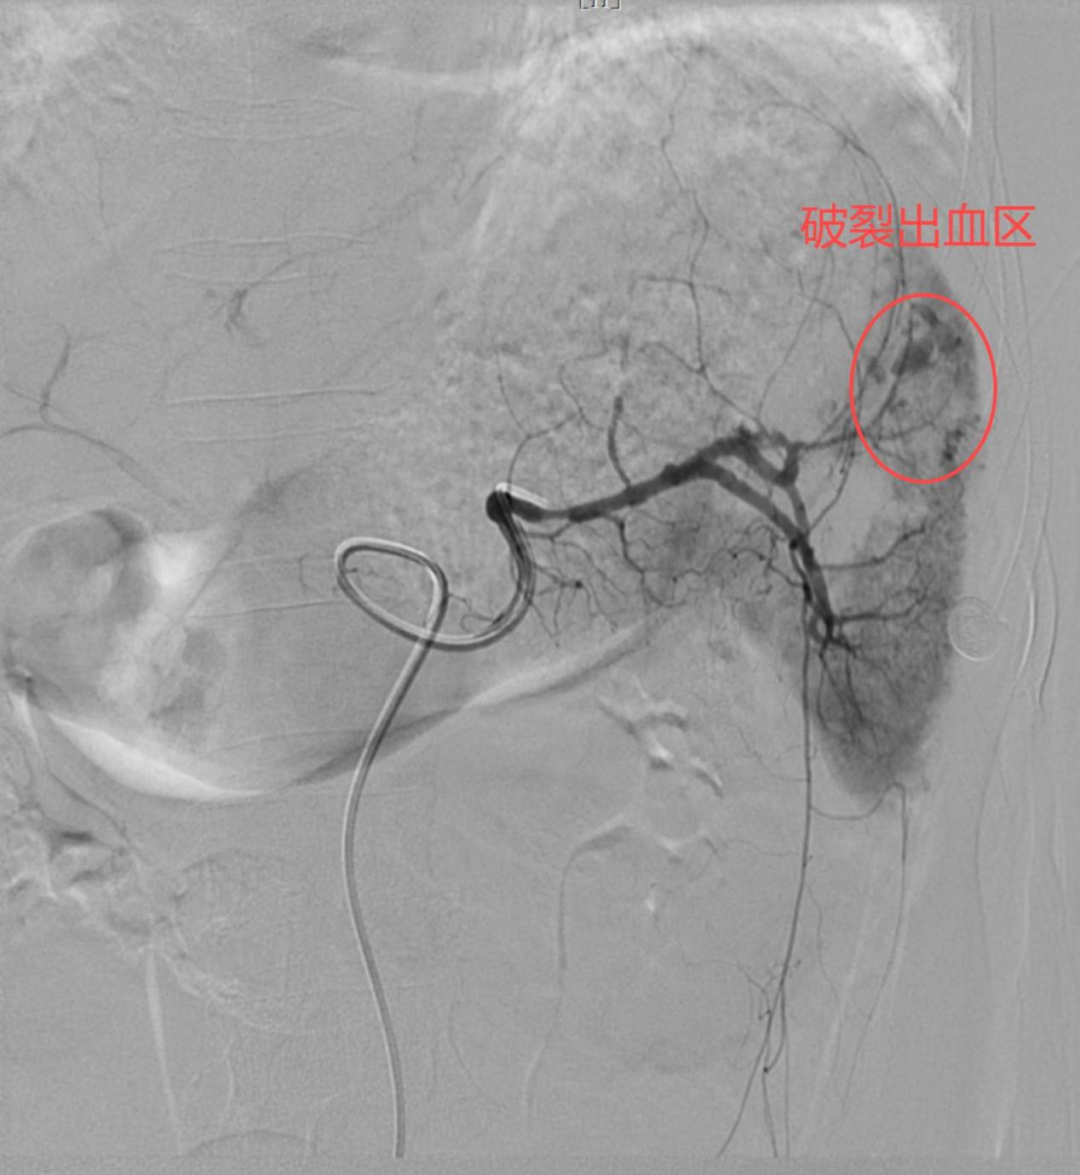

1、找到“漏水点(出血点)”。

通过血管造影定位破裂血管,用栓塞材料封堵出血点,避免开腹手术。